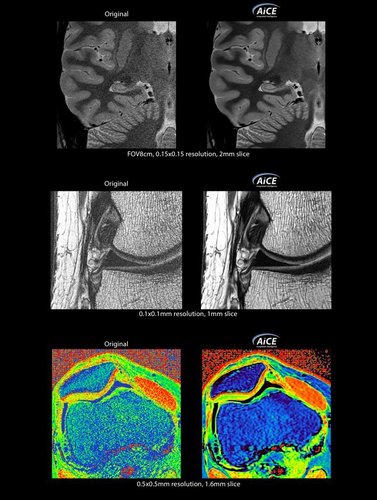

KI-optimiertes Arbeiten und modernste 3T-Technologie machen den Vantage Galan 3T von Canon Medical aus. Canons KI-Anwendung AiCE, kurz für Advanced intelligent Clear-Imagequality Engine, entfernt intelligent das Rauschen und führt zu einer Verbesserung des SNR (Signal-Rausch-Verhältnis). Mit Hilfe der Deep Learning Technologie gelingen besonders klare und deutliche Bilder. Insgesamt ermöglicht die KI-Unterstützung des Vantage Galan 3T somit nicht nur eine höhere Auflösung der Bilder, sondern verkürzt in vielen Fällen auch die Aufnahmezeit.

Mit der PURERF-Technologie und der PUREGradienten-Technologie werden das SNR um bis zu 20% verbessert und Diffusionsbilder optimiert.